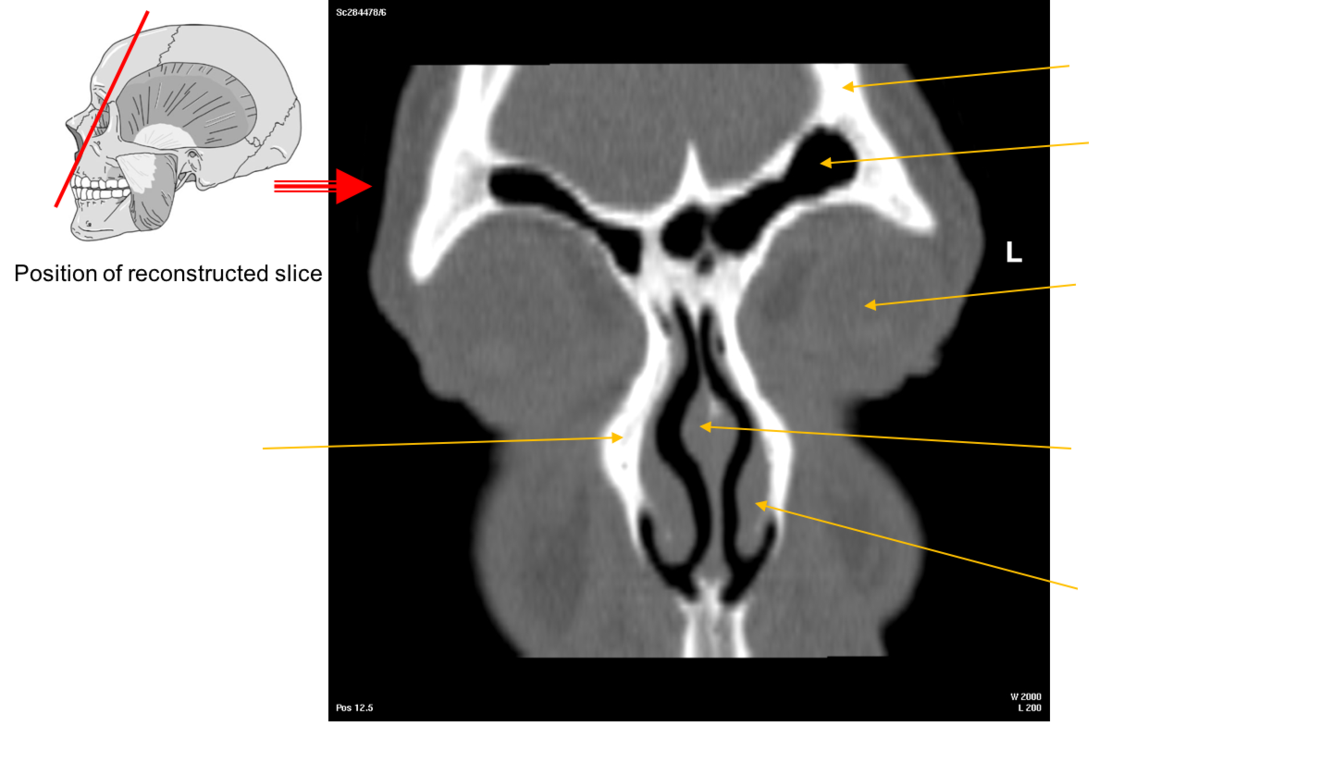

Label this image

Label image

The Nasal Conchae also called turbinates

These are thin scroll shaped bony plates that project into the nasal cavity. There are usually three the superior, middle and inferior nasal conchae (supreme may also be present).

•These conchae form passageways – the superior, middle and inferior meatae which are lined by mucous membrane

•This arrangement increases the surface area of the nasal cavities providing for rapid warming and humidification of air as it passes to the lungs.